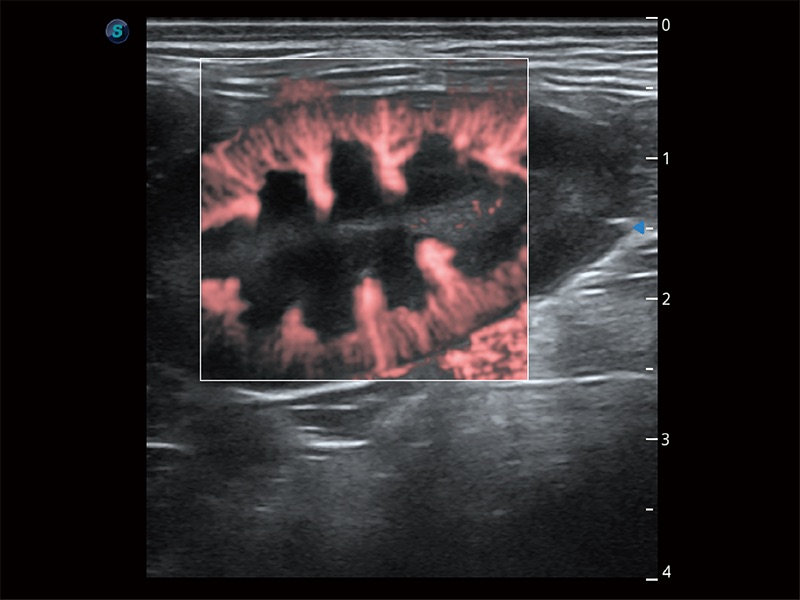

• Micro F 显微血流成像

极大提升超低速微细血流的检出能力,同时更精准地滤除软组织和超声信号,为兽用医生提供以往无法通过常规血流获得的疾病诊断信息。